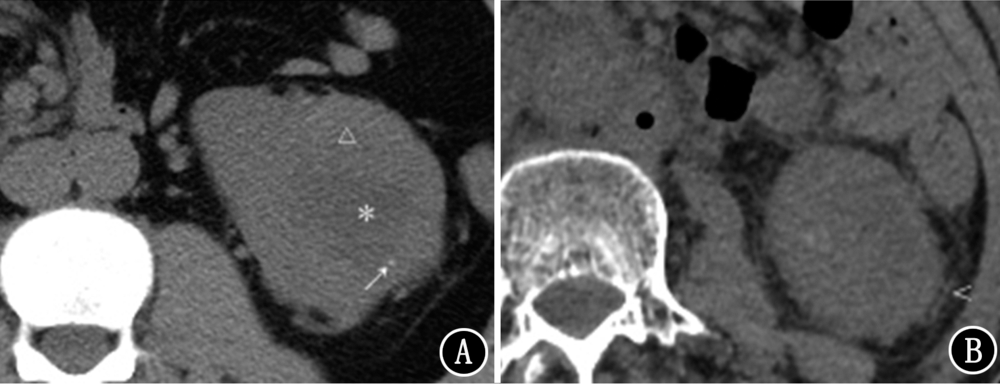

目的探讨肾透明细胞癌(ccRCC)患者术前CT征象影响总生存期的独立危险因素并绘制列线图。方法回顾性分析空军军医大学第一附属医院2011年10月至2015年12月术前行CT扫描并最终经病理学证实的ccRCC患者238例。由两名影像科医生对每例患者的CT征象进行评价,并收集患者的一般资料、肾功能检查以及世界卫生组织/国际泌尿病理协会(WHO/ISUP)分级。绘制Kaplan-Meier生存曲线,采用log-rank检验比较生存率。采用Cox比例风险回归进行单变量和多变量分析,并根据多变量分析结果绘制列线图,采用Bootstrap 1000法内部验证后计算C-指数。结果238例患者 经3~74个月随访后,死亡组32例,截尾组206例。死亡组患者的肿瘤直径为(65.70±27.29)mm,大于截尾组的(46.25±26.16)mm,差异有统计学意义(t=-3.889,P<0.001)。死亡组患者肿瘤坏死(χ2=45.716,P<0.001)、区域淋巴结肿大(χ2=43.342,P<0.001)、肾周脂肪侵犯(χ2=19.324,P<0.001)的发生率均高于截尾组患者。不同肿瘤直径的ccRCC患者其生存率差异有统计学意义(χ2=17.108,P<0.001)。肿瘤组织出现坏死患者的生存率较无坏死患者低(χ2=48.195,P<0.001);区域淋巴结肿大患者的生存率低于无区域淋巴结肿大的患者(χ2=47.232,P<0.001);出现肾周脂肪侵犯患者的生存率低于未侵犯的患者(χ2=19.964,P<0.001)。不同WHO/ISUP分级ccRCC患者的生存率差异有统计学意义(χ2=27.765,P<0.001)。多变量Cox比例风险回归分析结果显示,CT征象中的肿瘤直径(HR=2.90,95%CI为1.37~6.14,P=0.006)、坏死(HR=8.88,95%CI为3.33~23.69,P<0.001)及区域淋巴结肿大(HR=4.48,95%CI为2.04~9.86,P<0.001)是ccRCC患者死亡的独立危险因素。列线图的C-指数为0.870。结论术前CT征象与ccRCC患者的生存率存在相关性,其中肿瘤直径、肿瘤出现坏死以及区域淋巴结肿大是其死亡的独立危险因素,其列线图具有较高的准确性。